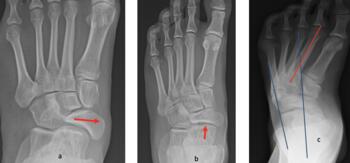

As the Ponseti grew in popularity, I noted significant discrediting of surgical options. Well long-term studies on the Ponsetti are starting to surface, and it is not without its own problems. Kids are lost to follow-up, not braced appropriately, and just like we saw in long-term studies with the posteromedial release, there is a lot of undercorrection. Casting cannot and will not ever achieve what the Cincinnati release can. Although the Ponseti may not have the complications of the Cincinnati, X-ray data reveals that the Ponseti cannot and does not correct everything, most critically, talocalcaneal angles. You can not solve a clubfoot with an Achilles tenotomy and an overly aggressive casting. As these kids develop, I see residual met adductus and calcaneal varus, along with casting complications like flat top talus and met primus elevatus. I then see that they will develop DJD just like posteriomedial and Cincinnati releases. Haasbeck and team in 1997 reported that the Cincinnatti required fewer procedures than the posteromedial release over the life of their study.14 Thomas performed a systematic review in 2019, concluding that the longer the study follow-up, the greater the relapse rate and the poorer the results of the Ponseti.15 For most of us who have done clubfeet surgery for many years, this is no surprise. Among the 46 studies meeting inclusion criteria, they saw as high as 67 percent required future surgeries to address relapse.15

One of the most disturbing complications with any casting is the development of flat top talus. Overly aggressive attempts to dorsiflex the ankle often lead to met primus elevatus, but the flat top talus ruins the ankle joint during development. When I work with residents and students, I always stress the importance of avoiding dorsiflexion completely during the casting phase simply because I do not want to create a deformation of the talus. I reserve all of my sagittal plane correction for the Achilles lengthening and posterior capsule release. Unfortunately, I see more and more cases of flat top talus as a result of the Ponseti method. Khan and colleagues in 2021 reported a significant increase in their study and review of the literature, blaming it solely on overly aggressive casting and manipulation.16

Here is a typical case presentation. A 21-year-old Marine at Ft. Leonard Wood for training underwent a Cincinnati release at one year old and had stellar follow-up. Her surgeon even wrote her medical waiver for entrance into the Marines. She ran track in high school. She finished boot camp and completed all of her Marine training, but now has chronic pain. She no longer can run. She hasn’t passed her physical training in over a year. She developed talonavicular DJD. By all accounts, her overall clubfoot should be rated an A+; no residual deformity, normal talocalcaneal angles on AP and lateral views, no equinus, no residual varus, only slight met primus elevatus, but no signs of a flattop talus. Clinically, she lacks subtalar range of motion, which I commonly find post-clubfoot release of any kind. So many in the military do very well for a while, but the demands of the military eventually catch up to them. We all root for clubfeet to make it, but the odds are stacked against them.